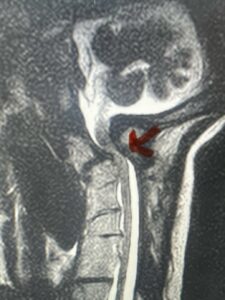

Fig. 4a: Sagittal T2-weighted cervical MRI demonstrating severe cord compression with myelomalacia of upper cervical spinal cord (red arrow). Notice the increased atlanto-dens interval (red dot).